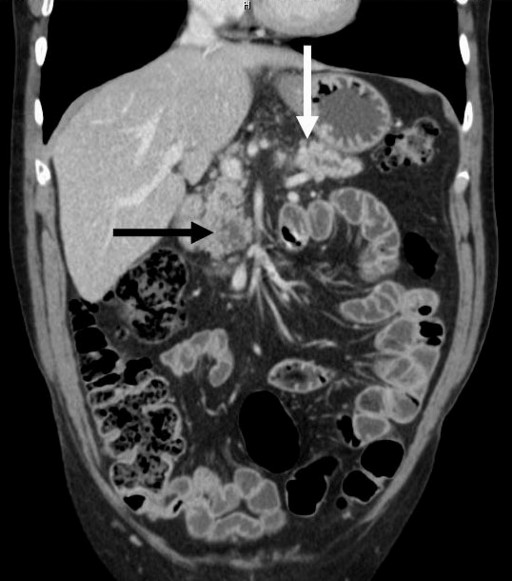

A 56-year-old man was admitted to our hospital for recurrent pancreatitis. Noteworthy aspects of his medical history included alcohol and tobacco consumption, an ischemic stroke related to right carotid aneurysmal rupture and hypertension. Following the stroke, he suffered from left hemiplegia and epilepsy. Although he no longer consumed alcohol, he had been treated for two episodes of acute pancreatitis during the previous year. He complained of epigastric pain at the time of the consultation (his medical treatment included 40 mg of morphine orally per day) and, upon physical examination, he was found to have left hemiplegia without jaundice, fever or weight loss. Abdominal palpation did not detect any abnormal mass and laboratory examination revealed no hyper-leucocytosis or anemia. Hepatic and pancreatic enzymes were slightly increased (ALT: 52 IU/L, reference range: 0-41 IU/L; AST: 43 IU/L; reference range: 0-38 IU/L; lipase: 264 IU/L, reference range: 114-286 IU/L; amylase: 100 IU/L; reference range: 25-115 IU/L), but there was no biological cholestasis. An abdominal CT scan showed a polycystic lesion, 26 mm in diameter, located in the uncus. This lesion was associated with a concurrent stenosis of the isthmic pancreatic duct which resulted in a distal dilation (Figure 1). Following an endoscopic ultrasound and MRI, the cystic lesion was characterized as a typical branch-type IPMT and the ductal dilation was attributed to chronic pancreatitis (Figure 2). The final diagnosis was, therefore, of chronic pancreatitis related to an IPMT of the uncus. A surgical resection of this IPMT was carried out. A Whipple procedure was then performed with extemporaneous histological analysis of the pancreatic cut edge, revealing the presence of malignant cells. In view of these histological findings, the pancreatic incision was shifted 3 cm to the left of the pancreatic isthmus, revealing no malignant cells upon extemporaneous histological analysis. Definitive histological analysis confirmed the diagnosis of an IPMT in the uncinate process (Figure 3) as well as a concurrent adenocarcinoma, 1 cm in diameter, located 2 cm from the primary IPMT, in the isthmus (Figure 4). The patient had an uneventful postoperative course and was discharged from the hospital 15 days following surgery. The patient subsequently underwent adjuvant chemotherapy. He is alive without recurrence 7 months following the surgery. Upon postoperative review of the original CT scan, we noted that the stenosis which was initially attributed to chronic pancreatitis was, instead, due to a lesion that we had not originally identified and which corresponded to the concomitant adenocarcinoma.

Figure 1. Abdominal CT scan: polycystic lesion in the uncus (black arrow) concomitant with a concurrent stenosis-dilation of the pancreatic duct. A detailed review of the original pancreatic CT scan revealed that the stenosis was caused by a lesion, previously unidentified, corresponding to an independent adenocarcinoma (white arrow). |